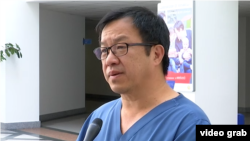

Юрий Пя, ҷарроҳи қалб, ки солҳои тӯлонӣ дар хориҷа кор кардааст, мегӯяд, бояд ҷомеа ин вазъро дарк ва қабул кунад. Ӯ таҷрибаи Туркияро дар самти ба расмиятдарории васияти аъзои бадан мисол овард ва гуфт, “вақте барои шумо шаҳодатномаи ронандагӣ медиҳанд, дар тарафи дигараш навишта шудааст, ки дар сурати марги мағзӣ ман ин ва ё он аъзоямро васият мекунам. Ин ҳаққи шумо аст, ки навиштаҷотро пур мекунед, ё не. Шумо метавонед розӣ шавед ё рад кунед.”